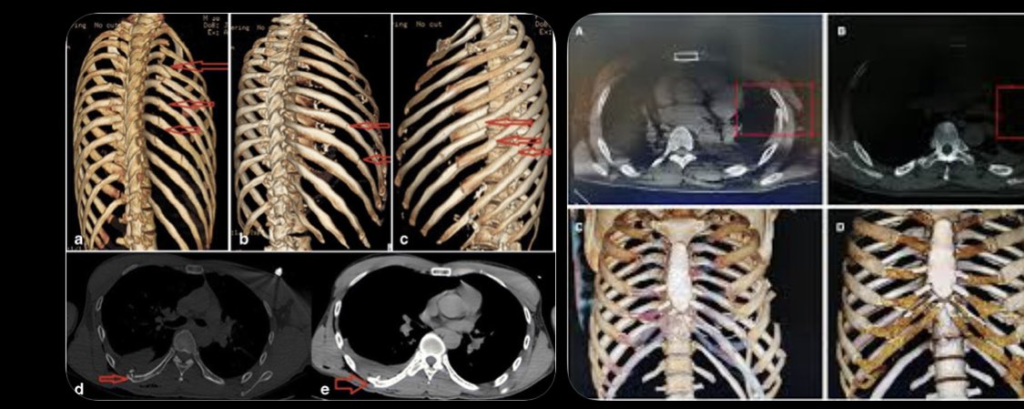

A través de redes sociales, Corey compartió imágenes desde el hospital y explicó que el choque le provocó la fractura de 11 costillas, o como él mismo lo describió: “11 cosas en mis costillas”. Incluso contó que pasó tres noches internado debido al impacto.